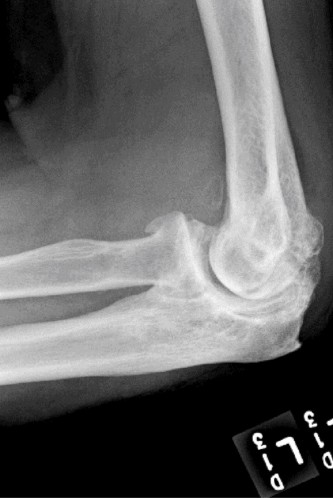

Examination reveals deformity about the elbow with no open lesions or skin tenting. He has a palpable radial and ulnar pulse and is neurologically intact. His images are shown (Figs. 2–85 to 2–88).

Figure 2–85

Figure 2–86

Figure 2–87

Figure 2–88

What is the diagnosis and direction of displacement?

- Monteggia fracture dislocation, posterolateral displacement of the forearm about the humerus

- Simple elbow dislocation, posterolateral displacement of the forearm about the humerus

- Transolecranon complex elbow dislocation

- Simple elbow dislocation, posteromedial displacement of the forearm about the humerus

Discussion

The correct answer is (B). This is the most common type of elbow dislocation, and often does not cause any osseous injury. Posterolateral and posteromedial dislocation account for approximately 90% of dislocations. Adequate pre- and postreduction films are necessary to evaluate for fracture, which would change the classification to a complex injury.